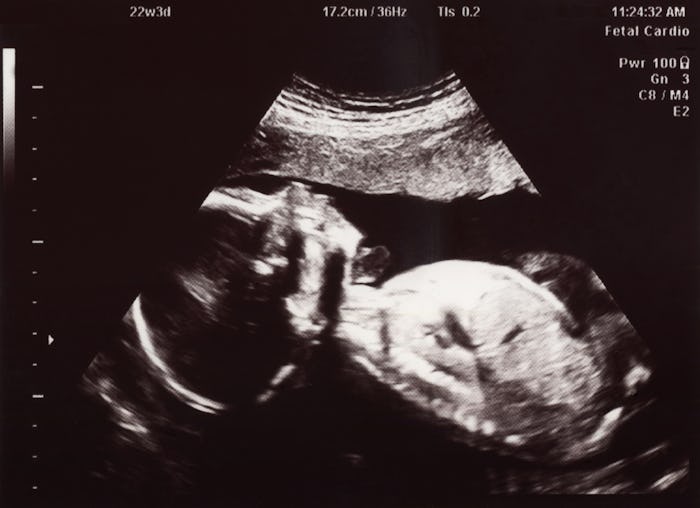

When your baby is growing and developing, something about life inside the womb may give you pause, particularly about your baby's oxygen intake. For instance, how can babies breathe in amniotic fluid? The womb is a totally liquid environment, after all, and last you checked, humans don't have gills like fish. This may come as a surprise, but learning how to breathe in general takes a lot of time, development, and effort from the baby, and it's a fascinating process.

In a technical sense, though, babies do not really breathe in amniotic fluid. (Although it would be cool if your developing fetus were literally breathing under water, right?) A baby's first true breath occurs at birth when he initially begins to cry, according to the website for Dr. Sears. However, babies in the womb do practice the movements required for breathing, and they start going through the motions pretty soon. Consider it a sort of warm-up period. As early as week 10 or 11 of growth, developing fetuses will practice inhaling tiny portions of amniotic fluid, as noted by Healthline. At first the movements are more like swallowing, but as the baby nears his due date, the movements take on a more breath-like appearance. It is all a way to prepare those muscles and reflexes for that big initial breath.